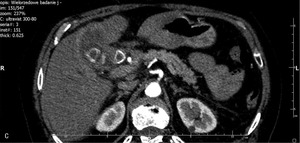

U chorej wykonano badanie TK z fazą pokontrastową (ryc. 2A-C).

Spośród wymienionych wyżej jest to metoda optymalna ze względu na koszt i dostępność oraz wartość diagnostyczną. Badanie wykluczyło obecność złogu w jamie otrzewnej, potwierdzając jednocześnie występowanie zwapnień pozapalnych w dnie pęcherzyka żółciowego i rozległego nacieku w sąsiadującym miąższu wątroby. Obraz zmiany i charakter wzmocnienia w fazie tętniczej (ryc. 2C) nie pozwalają na różnicowanie zapalenia i nacieku raka pęcherzyka żółciowego.

U chorej wykonano zabieg biopsji cienkoigłowej zmian ogniskowych wątroby zlokalizowanych w sąsiedztwie pęcherzyka żółciowego. Wyniki badania cytologicznego bioptatu potwierdziły obecność raka pęcherzyka żółciowego.